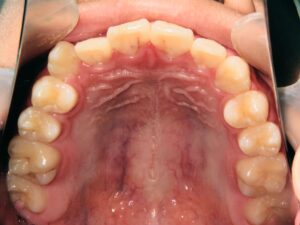

第1期治療開始時

顔貌写真

口腔内写真

年齢

9歳 男性

主訴(患者様のお悩み)

歯のデコボコを治したい

診断

上顎前歯部叢生(上の前歯のデコボコ)

上下顎側切歯クロスバイト(部分受け口)

上顎狭窄歯列(上のあごが小さめ)

歯冠幅径大(歯が大きめ)

治療方針

上顎緩徐拡大(上あごを拡大)

上の前歯部のみワイヤー矯正

使用装置

緩徐拡大装置(クワドヘリックス)

前歯部ブラケット

治療期間の目安:約半年~1年(保定期間を除いた期間)